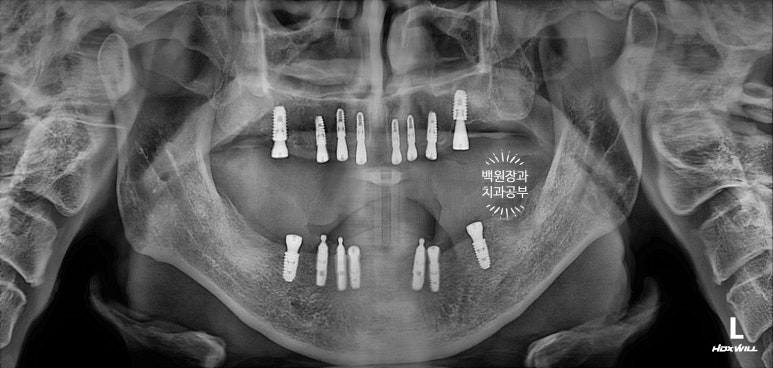

위턱은 전체 틀니를 사용하고 계셨고, 아래턱에는 임플란트 틀니 (오버덴처)를 사용하고 계셨습니다.

위턱은 치아가 하나도 없으신 상태였고, 전체 틀니를 사용 중이셨지요.

아래턱은 임플란트 네개가 있었지만, 위치가 약간 제각각이네요.

정면과 측면 구강 내 사진입니다. 아래 임플란트가 임플란트 주위염을 앓고 있어 보이지 말아야 할 임플란트의 뿌리부분이 보이네요...